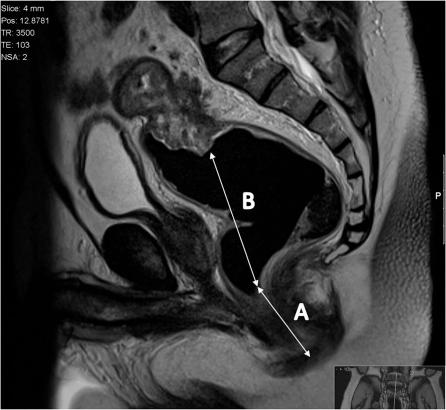

基于表格的直肠癌报告。

Proforma-based reporting in rectal cancer.

The improvements in outcomes associate with the use of preoperative therapy rather than postoperative treatment means that clinical teams are increasingly reliant on imaging to identify high-risk features of disease to determine treatment plans. For many solid tumours, including rectal cancer, validated techniques have emerged in identifying prognostic factors pre-operatively. In the MERCURY study, a standardised scanning technique and the use of reporting proformas enabled consistently accurate assessment and documentation of the prognostic factors. This is now an essential tool to enable our clinical colleagues to make treatment decisions. In this review, we describe the proforma-based reporting tool that enables a systematic approach to the interpretation of the magnetic resonance images, thereby enabling all the clinically relevant features to be adequately assessed.

摘要

术前治疗而非术后治疗带来的结果改善意味着临床团队越来越依赖于影像学来识别疾病的高危特征以确定治疗方案。对于许多实体瘤,包括直肠癌,已经出现了用于术前识别预后因素的验证技术。在 MERCURY 研究中,标准化的扫描技术和报告表格的使用使得对预后因素的准确评估和记录成为可能。这现在是我们的临床同事做出治疗决策的重要工具。在这篇综述中,我们描述了基于报告表格的报告工具,它使我们能够对磁共振图像进行系统的解读,从而能够充分评估所有与临床相关的特征。